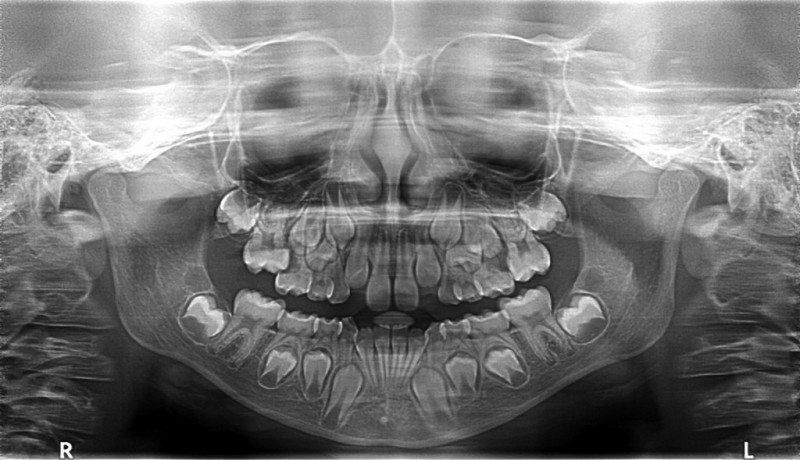

Életünk során két garnitúra természetes fogazat áll rendelkezésünkre – a harmadikról már egyénileg kell gondoskodnunk. Az ún. tejfogakat, amelyek körülbelül 6 hónapos korban jelennek meg, 6 éves kortól váltják le maradandó fogaink.

| Fogváltás: a 20 tejfogat kilökő 32 maradandó fog fejlődik az állcsontban. |